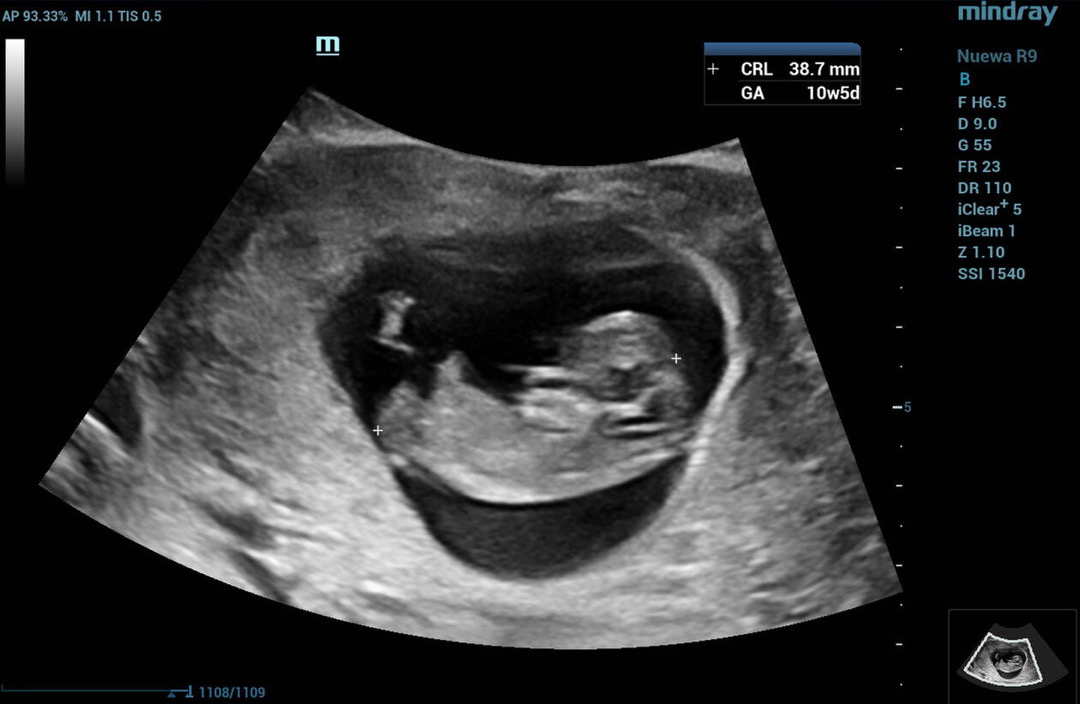

10주5일 초음파 심박수

안녕하세요 오늘로 10주5일차로 니프티 및 초음파를 보고왔어요 :) 작년 유산과는 달리 10주까지 잘커준 애기덕분에 행복한 나날들을 보내구있어요! 다름이 아니라 혹시 10주에 심박수가 다들 빠르던데 저희애기는 159정도라 의사는 괜찮다고 했지만 걱정이 돼서요.. 혹시 10주차에 159-160정도이신분들도 계실까요? 귀여운 사진 올려봅니다>,<